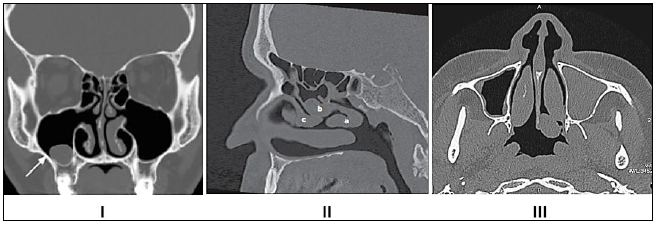

A afirmativa a seguir contextualiza a questão. Leia-a atentamente.

“Através do estudo anatômico, compreendemos a importância das imagens radiológicas do esqueleto axial e apendicular, sem distinção quanto à forma de aquisição, analógica ou digital.”

Com base na imagem radiológica apresentada, os números expostos referem-se, respectivamente, a quais estruturas anatômicas?